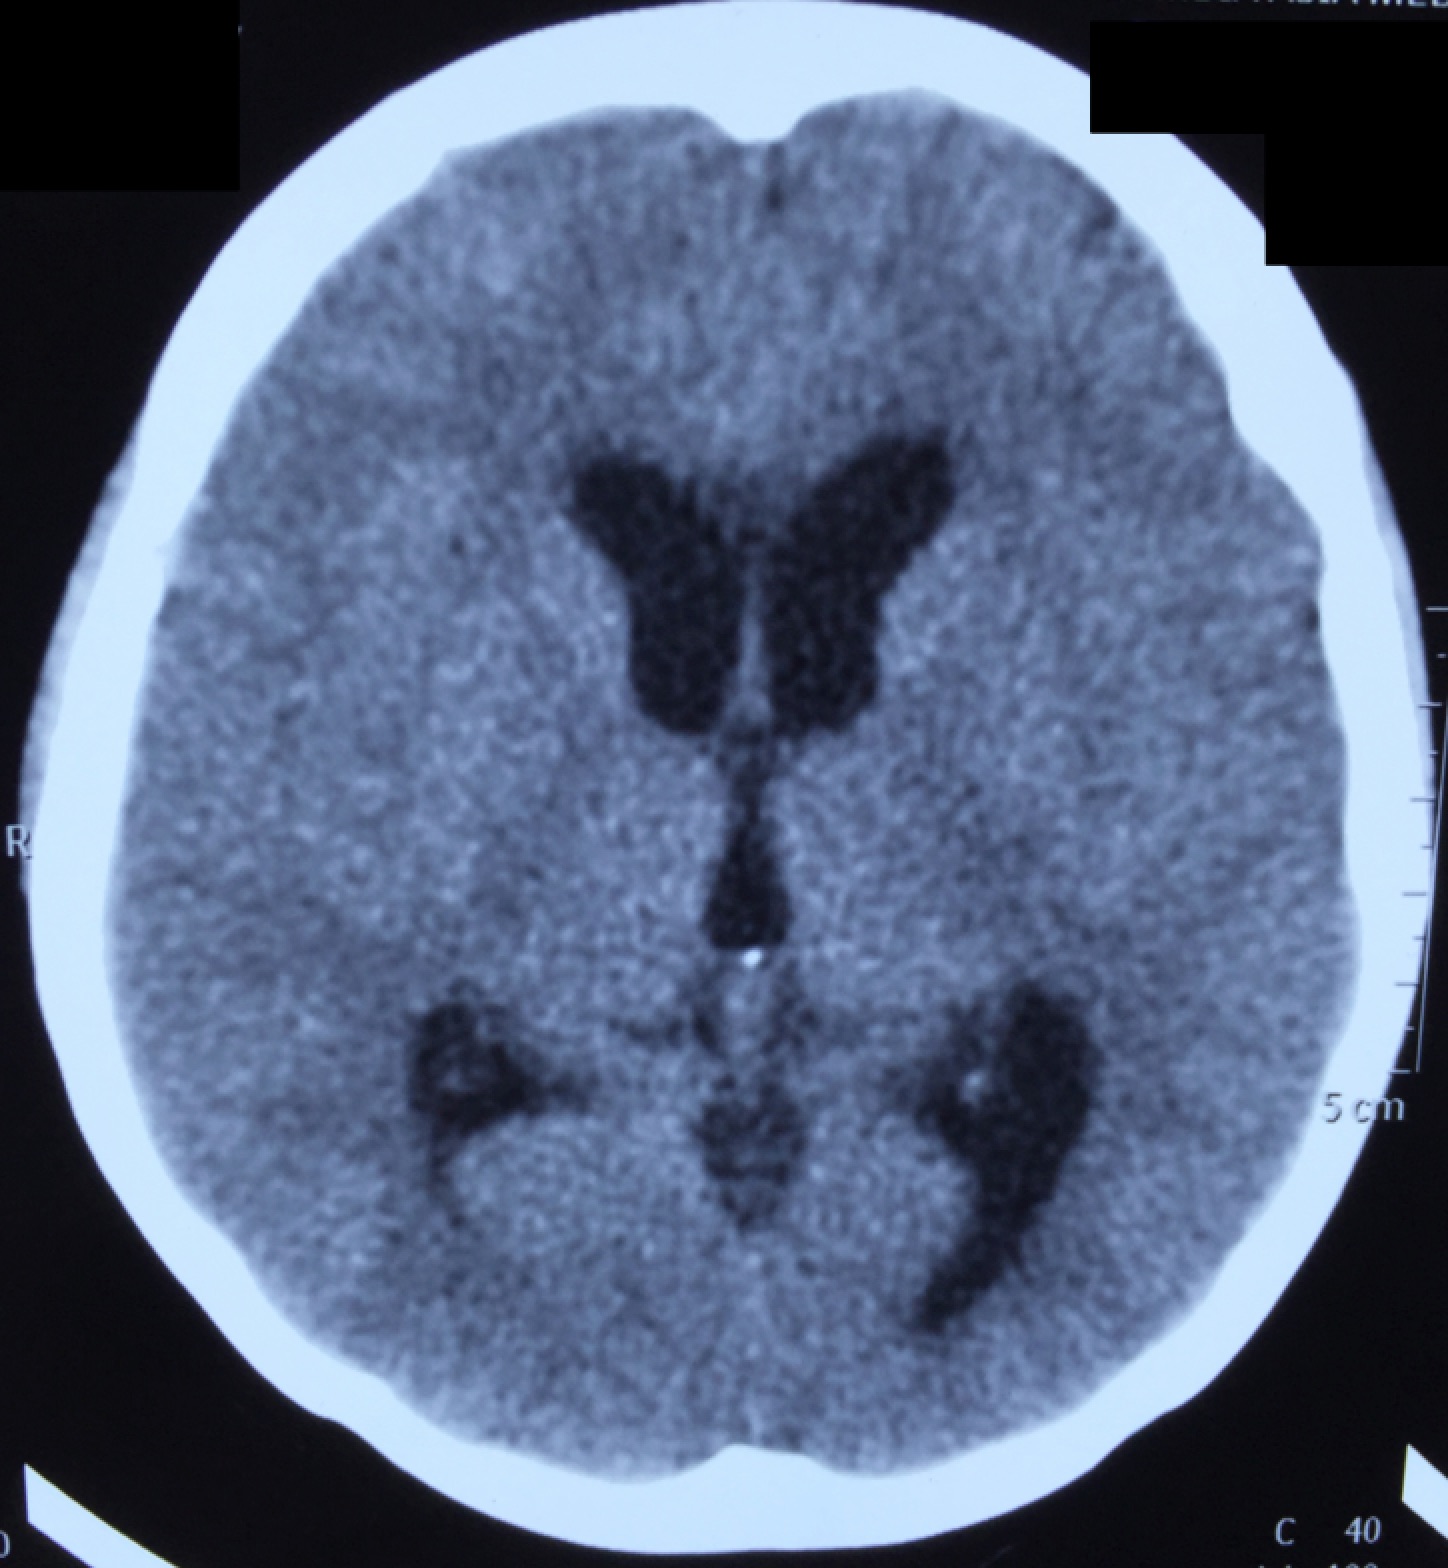

CT-head-1